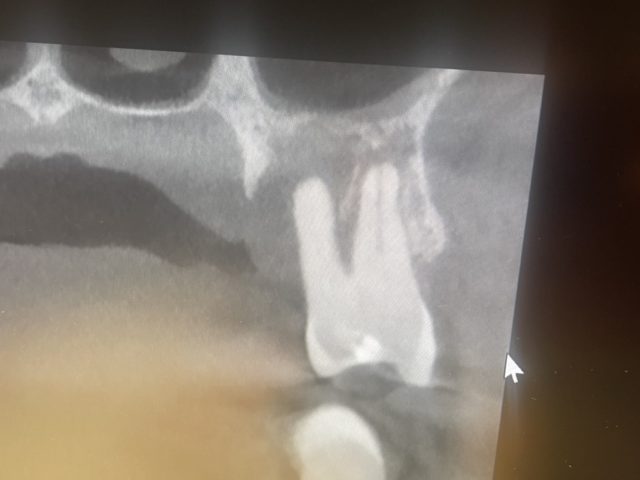

やっぱりCTは良いですね!分かりにくかった根管の形態もこんな感じで把握できます。

骨の厚みや高さも分かるので、インプラントの診断に活用されます。